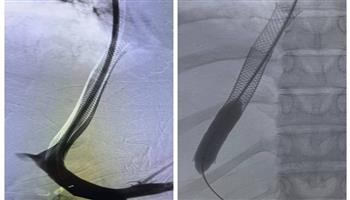

نجح فريق طبي بمستشفى الراجحي الجامعي للكبد بجامعة أسيوط، في إنقاذ حياة فتاة تبلغ من العمر ٢٢ عاماً، تعاني من فشل كبدي حاد نتيجة إصابتها بـ "متلازمة باد كياري" (انسداد أوردة الكبد)، وذلك عقب إجراء عملية دقيقة لتركيب دعامات معدنية بين الوريد الأجوف السفلي والوريد البابي الكبدي باستخدام تقنية الـ (TIPSS)، تحت رعاية الدكتور أحمد المنشاوي، رئيس الجامعة، والدكتور علاء عطية، عميد كلية الطب ورئيس مجلس إدارة المستشفيات الجامعية، والدكتور شريف كامل مدير مستشفى الراجحي.

وأكد المركز الإعلامي للجامعة، في بيان اليوم الجمعة - استقرار حالة الفتاة وخروجها من المستشفى بصحة جيدة، بعد المتابعة الدقيقة من الفريق الطبي ، والذي تشكل من قسم الأشعة التشخيصية والتدخلية والتصوير الطبي، تحت إشراف الدكتور حسن مجلي، رئيس القسم، وبقيادة الدكتور هاني سيف، أستاذ الأشعة التدخلية، يعاونه كل من، الدكتور سيد حسن، أستاذ مساعد الأشعة التدخلية، والدكتور مصطفى أحمد، مدرس بالقسم، والطبيب عمر جمال، مدرس مساعد بالقسم، والطبيبة رحاب محمد، طبيب مقيم بالقسم، و مهاب غانم، أخصائي التصوير الطبي، ومن قسم التخدير تحت إشراف الأستاذة الدكتورة هالة سعد عبد الغفار، رئيس القسم، الطبيب زكريا أحمد، طبيب مقيم بالقسم، ومن هيئة التمريض بوحدة الأشعة بالمستشفى، عزه كمال، مشرف التمريض، و هاجر أبو الخير.